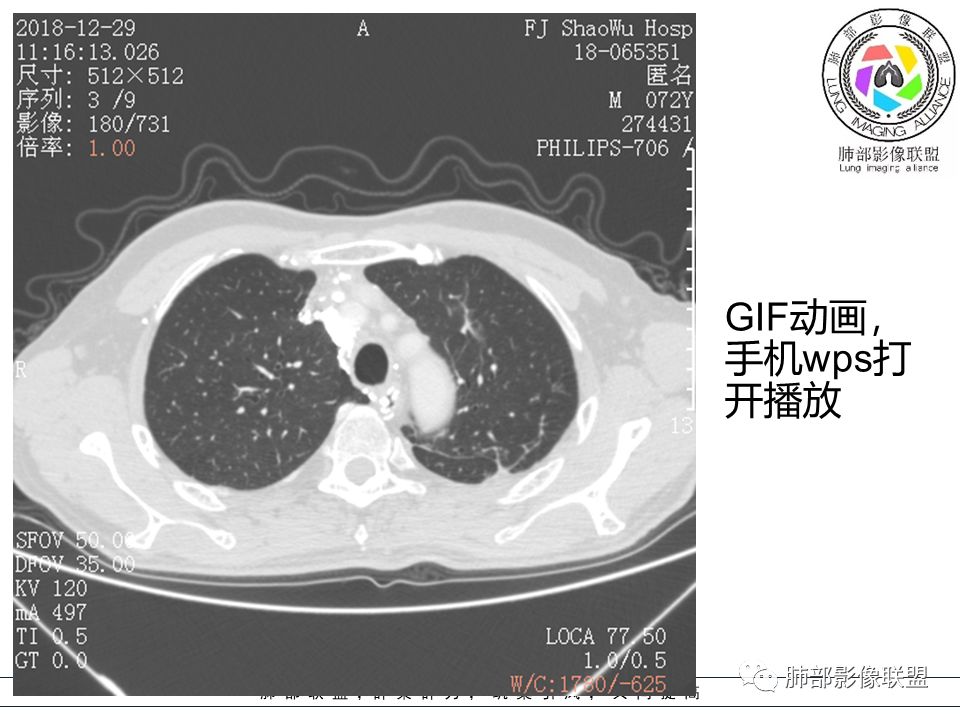

病例提供:邵武市立医院CT室 陈立君